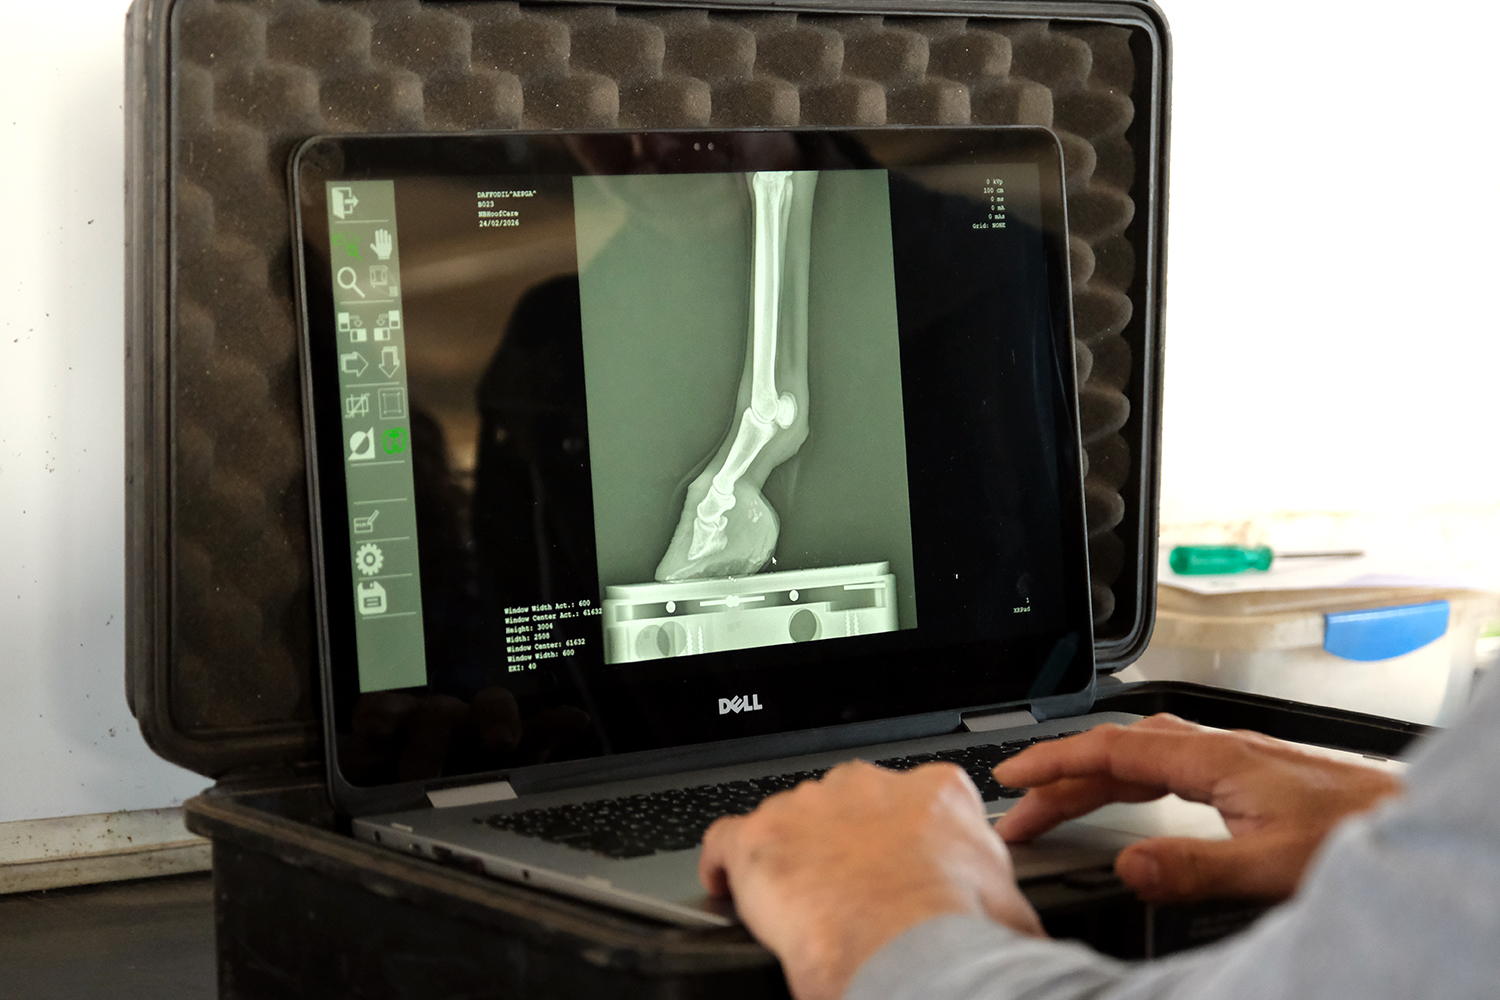

A AEPGA recebeu recentemente a visita do Médico Veterinário Nuno Bernardes, que realizou vários exames radiográficos a alguns dos animais da associação, com particular incidência na avaliação de cascos e dentes. Estes exames permitem observar com maior detalhe estruturas internas que não são totalmente acessíveis através do exame clínico, constituindo uma ferramenta importante no acompanhamento veterinário dos burros.

No caso dos cascos, a radiografia permite avaliar o posicionamento e a integridade das estruturas ósseas internas, nomeadamente da terceira falange, sendo fundamental para compreender o estado de saúde do casco de forma global. Esta informação é particularmente relevante no diagnóstico e acompanhamento da laminite, uma das patologias mais frequentes em asininos. A avaliação radiográfica permite apoiar decisões clínicas relacionadas com os cuidados podais, nomeadamente na definição do aparo corretivo mais adequado ou na eventual necessidade de recorrer a apoios artificiais, de forma a melhorar a distribuição de cargas e contribuir para o conforto e funcionalidade do casco. Importa salientar que, quando alterações estruturais como rotação ou afundamento da terceira falange já são visíveis radiograficamente, a laminite encontra-se geralmente numa fase crónica. Nestes casos, o objetivo do acompanhamento passa sobretudo pela gestão da doença e pela manutenção da melhor qualidade de vida possível para o animal. Por esse motivo, a prevenção assume um papel central no controlo desta afeção.